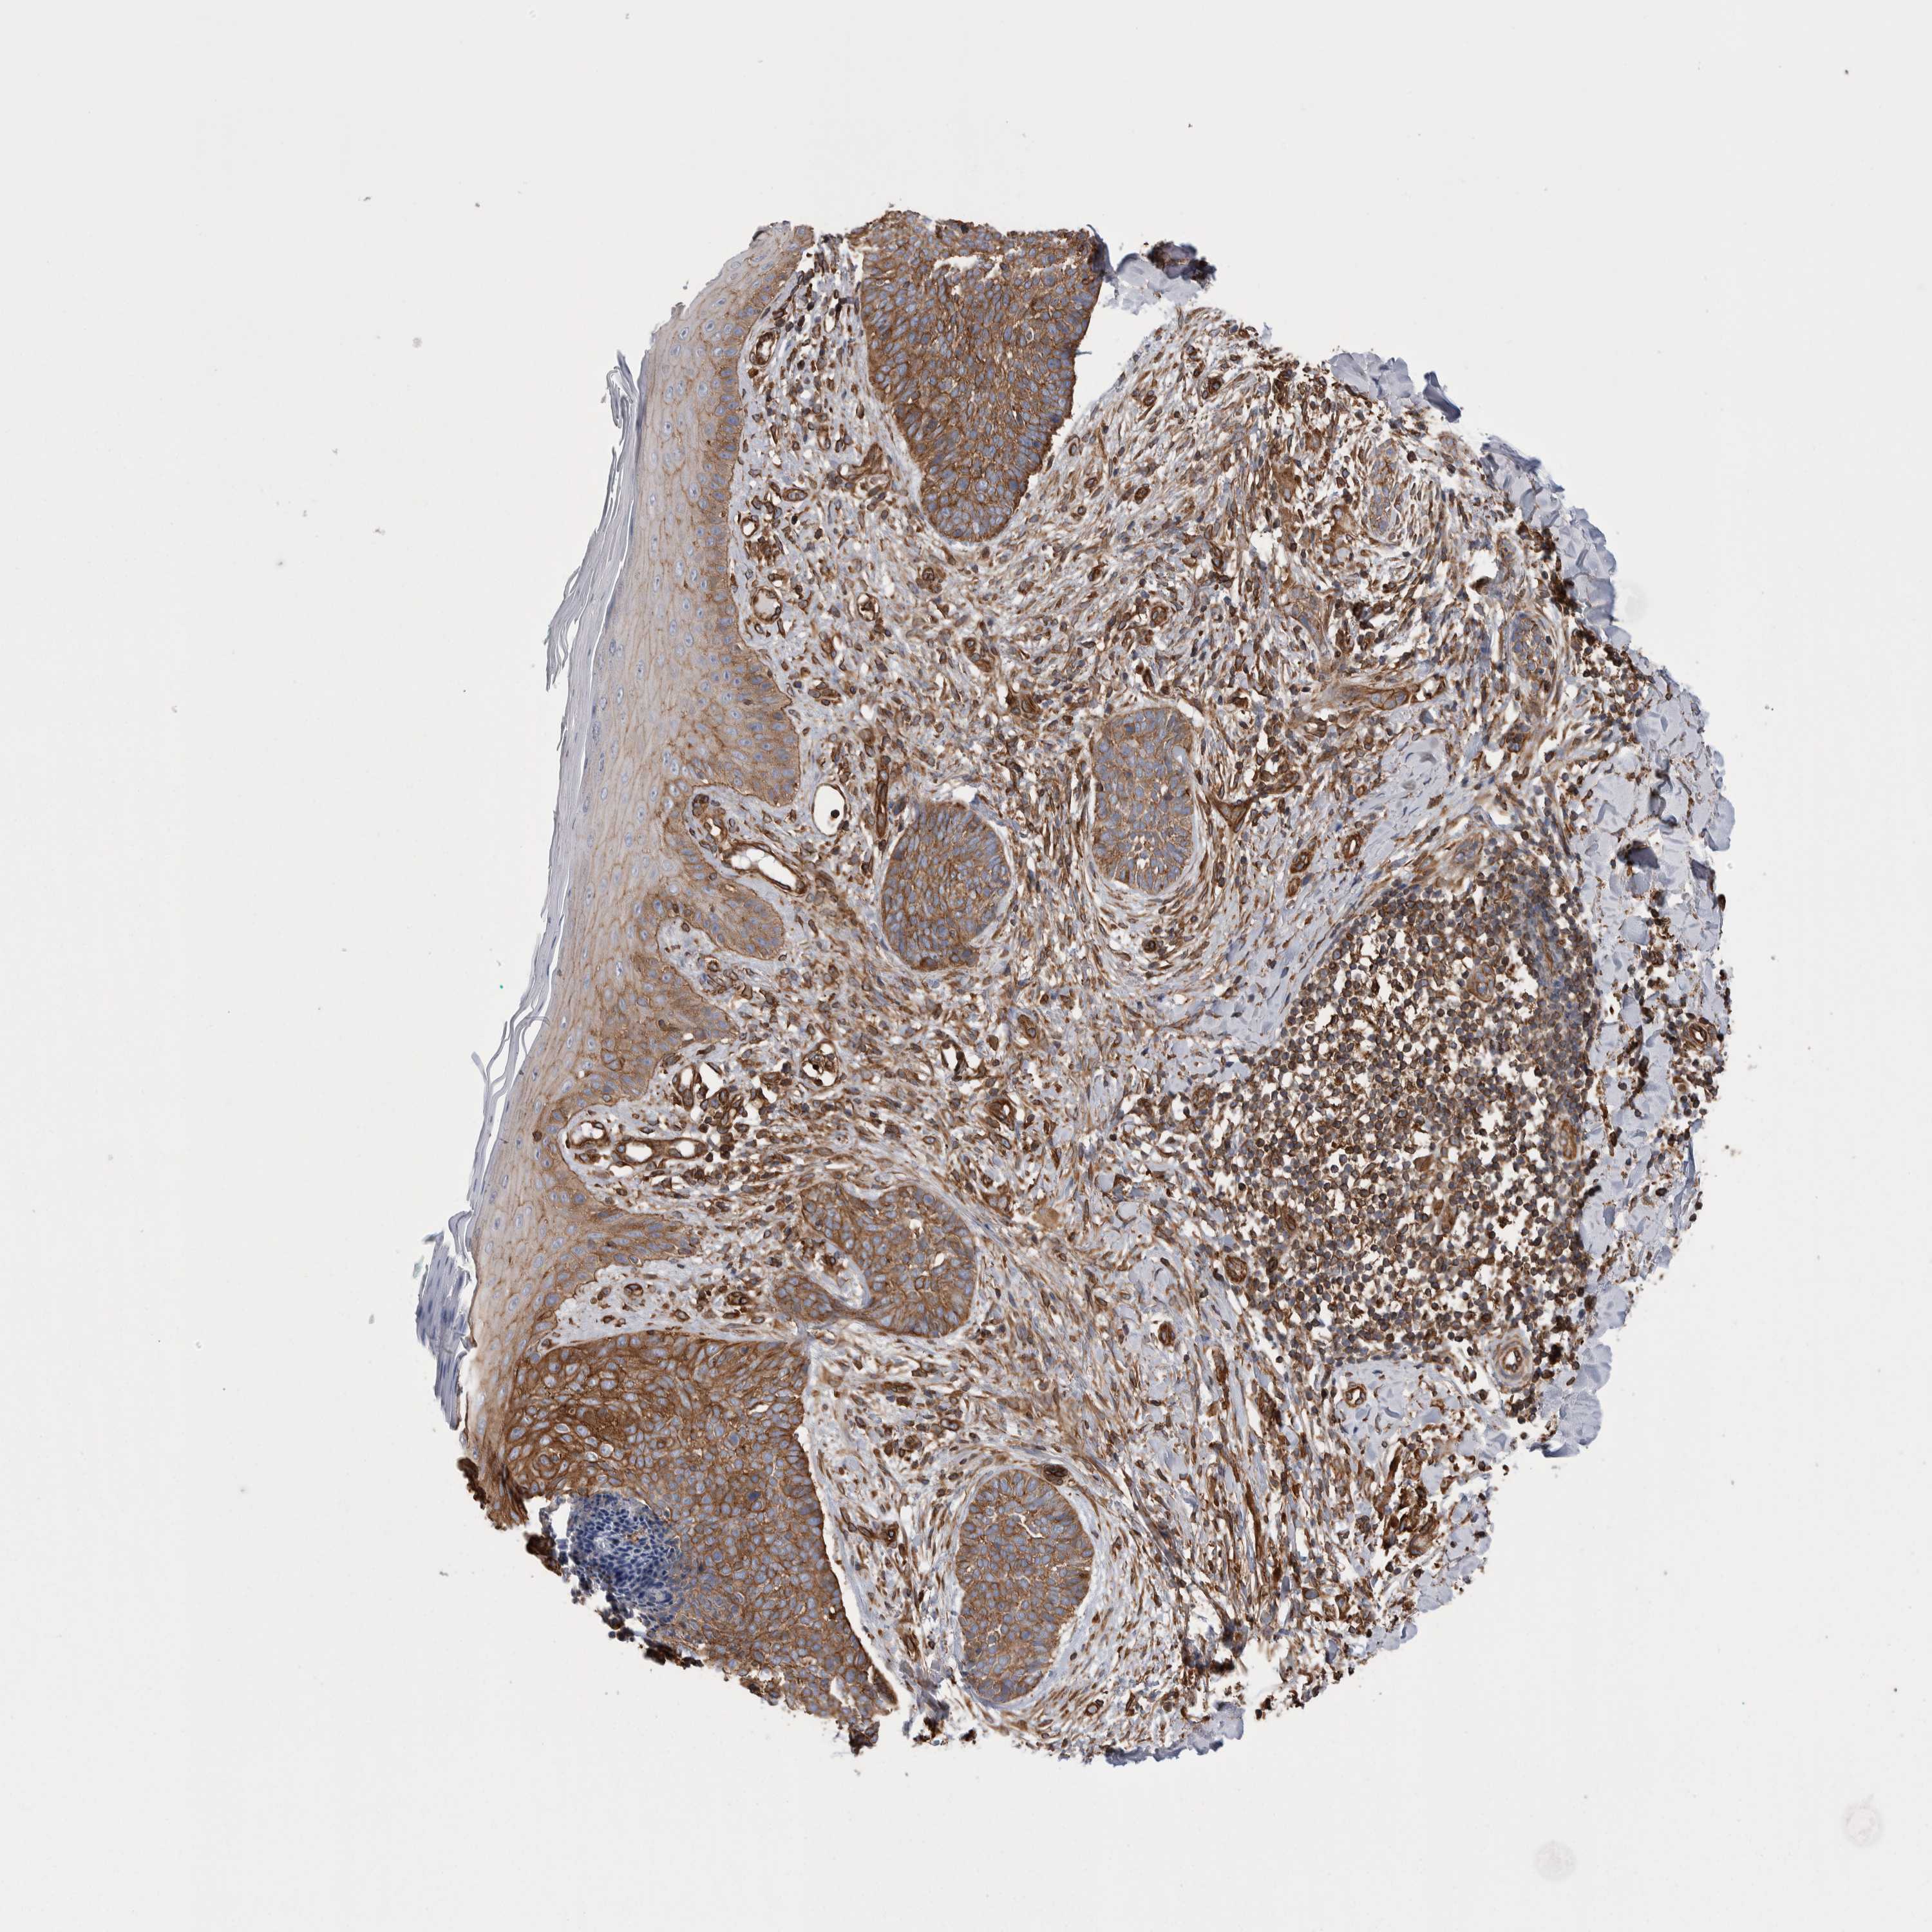

Basal cell and squamous cell cancer

SKIN CANCER - Protein expressioni

A mouse-over function shows sample information and annotation data. Click on an image to view it in a full screen mode. Samples can be filtered based on level of antibody staining by selecting one or several of the following categories: high, medium, low and not detected. The assay and annotation is described here.

Antibody stainingi

Antibody staining in the annotated cell types in the current human tissue is reported as not detected, low, medium, or high, based on conventional immunohistochemistry profiling in selected tissues. This score is based on the combination of the staining intensity and fraction of stained cells.

Each image is clickable and will lead to virtual microscopy that enables deeper exploration of all samples and also displays staining intensity scores, fraction scores and subcellular localization as well as patient and tissue information for each sample.

Antibody HPA020192

Antibody HPA024127

Staining

High

Medium

Low

Not detected

Intensity

Strong

Moderate

Weak

Negative

Quantity

>75%

75%-25%

<25%

None

Location

Nuclear

Cytoplasmic/membranous

Cytoplasmic/membranous,nuclear

Basal cell carcinoma